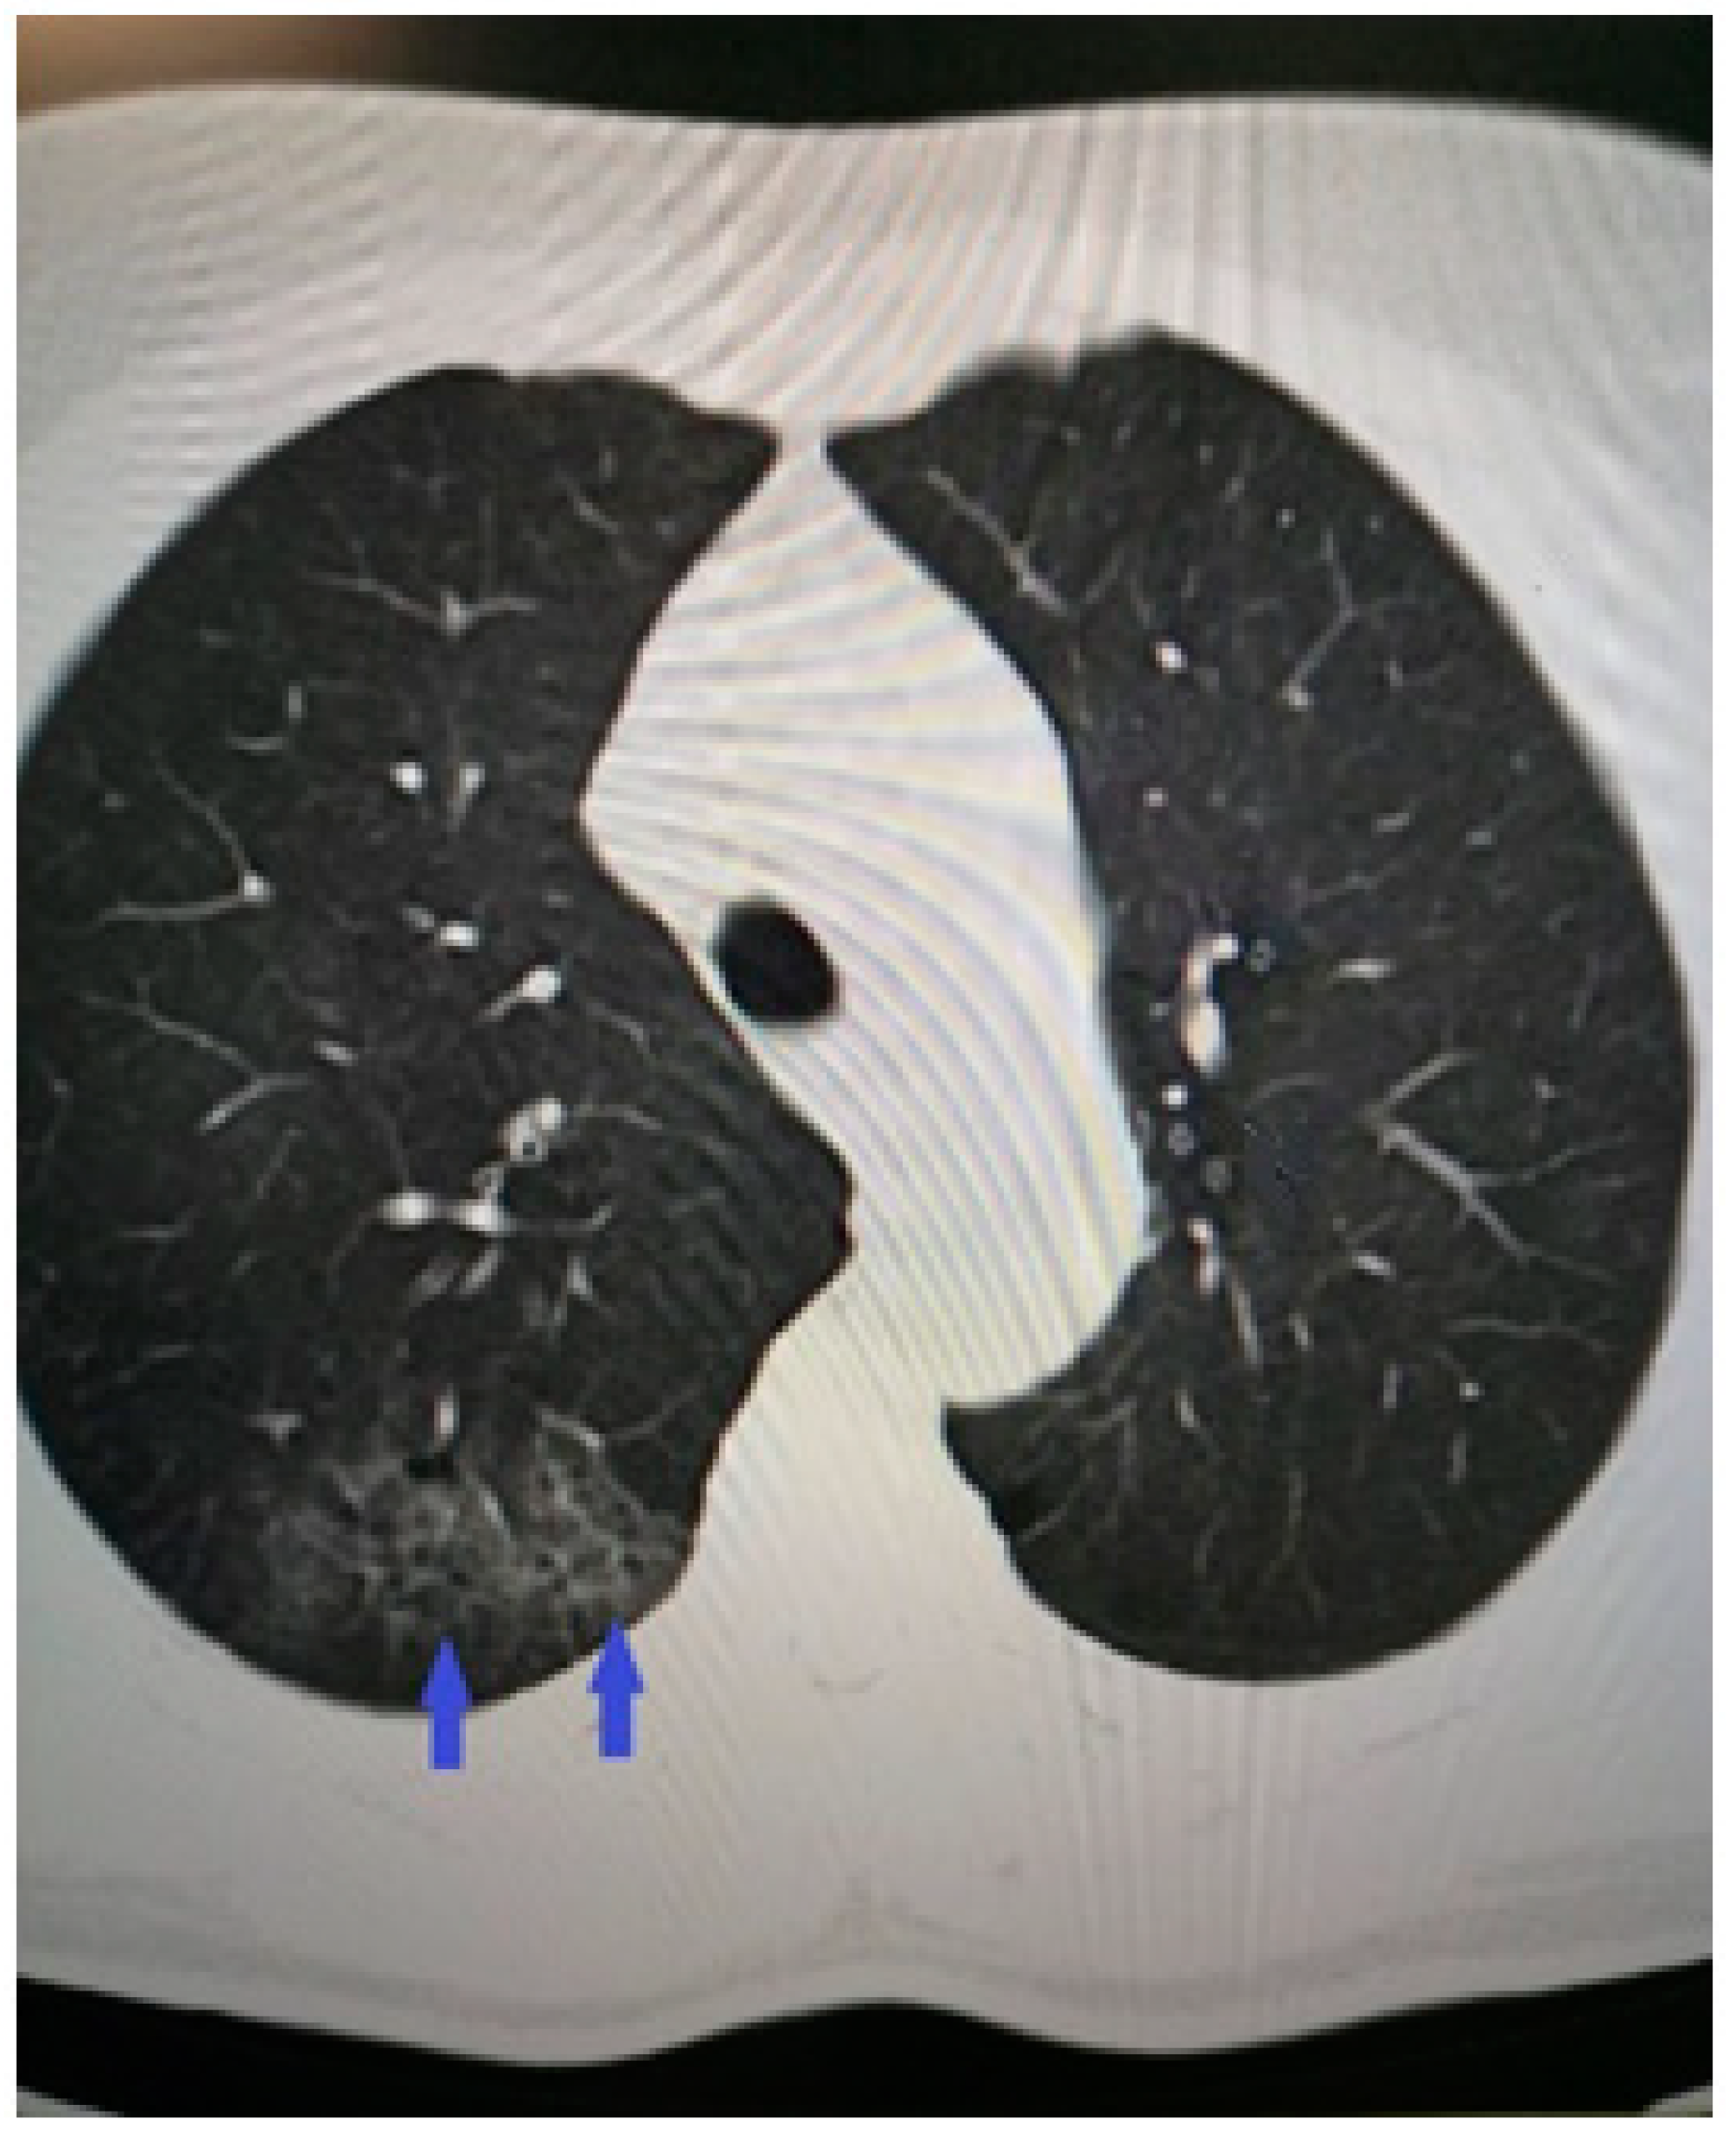

2. Case Presentation